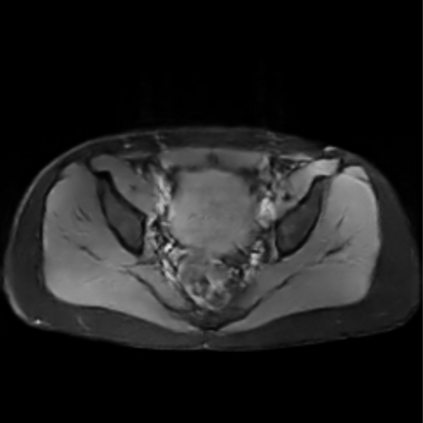

Motion artifacts are a primary source of magnetic resonance (MR) image quality deterioration with strong repercussions on diagnostic performance. Currently, MR motion correction is carried out either prospectively, with the help of motion tracking systems, or retrospectively by mainly utilizing computationally expensive iterative algorithms. In this paper, we utilize a novel adversarial framework, titled MedGAN, for the joint retrospective correction of rigid and non-rigid motion artifacts in different body regions and without the need for a reference image. MedGAN utilizes a unique combination of non-adversarial losses and a novel generator architecture to capture the textures and fine-detailed structures of the desired artifacts-free MR images. Quantitative and qualitative comparisons with other adversarial techniques have illustrated the proposed model's superior performance.